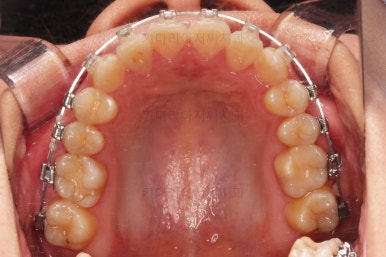

부산치아교정치과 전후 비교해 보겠습니다.

교합, 맞물림, 중앙선, 덧니, 입매, 앞니위치 및 각도 모든게 잘 마무리 되었습니다.

비발치로 오히려 입이 들어가게(악궁확장이나 치간삭제(공간확보의 목적) 없이도) 할 수 있었던 부산치아교정치과 좋은 치료였습니다.

이상 미니스크류를 이용해 비발치로 덧니를 개선하면서 입매도 오히려 뒤로 넣어주었던 부산치아교정치과 치료사례였습니다.